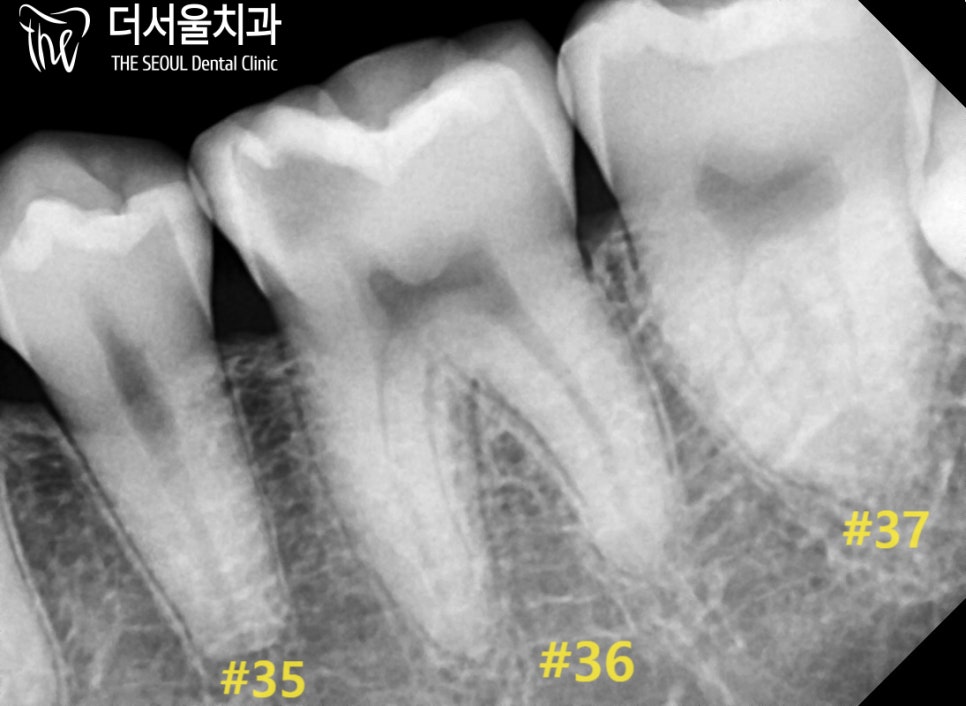

우선 심한 통증을 느끼고 있던 왼쪽 아랫니부터

순차적인 진료를 도와드리기로 했습니다.

비교적 깊게 썩어 있는 첫 번째 큰 어금니는

엔도를 진행하기로 했으며,

두 번째 어금니와 소구치는

인레이라는 부분 보철로

개선을 도와드리기로 했습니다.

순차적으로 치료를 진행했습니다.

어금니는 앞니에 비해 근관의 개수가 많고

더 복잡한 형태를 갖고 있기 때문에

더 꼼꼼하고 주의 깊은 과정을 필요로 합니다.

더서울에서는 클램프와 러버댐으로

멸균 환경을 만든 뒤에,

본격적인 신경치료를 시행했는데요.

뿌리 끝까지 확실하게 채워질 수 있도록

수차례 확인을 거친 후 밀폐를 마쳤습니다.